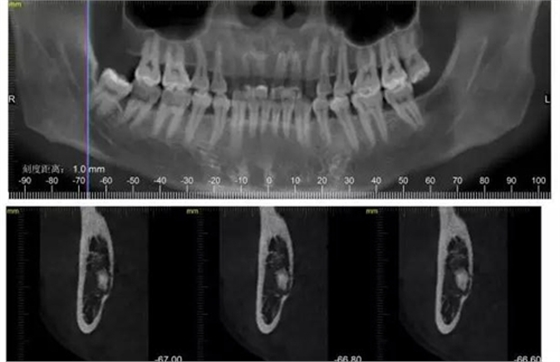

下面CBCT,可以看到兩個牙根的根尖三分之一在神經(jīng)管里面。

CBCT神經(jīng)管標(biāo)線,可以看到標(biāo)線不能連續(xù),中間被阻斷。